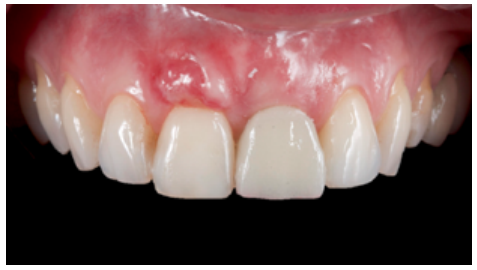

Clinical case: A 32-year-old female patient who attended for a possible root fracture of the upper left central incisor (ULCI), accompanied by a periodontal abscess at the bottom of the vestibule of the same tooth. A clinical and radiological examination established that the prognosis of the ULCI was unfavourable for conservative treatment. After evaluating the clinical features of the case, the treatment plan to extract the ULCI followed immediately by an osseointegrated implant (OII) and loading of a provisional prosthesis on the implant.

Conclusions: Rehabilitation on implants in situations of tooth loss in the aesthetic anterior sector, especially in young patients, requires a multidisciplinary treatment plan to extract the tooth and insert an OII in the correct 3-dimensional position. Various aspects need to be taken into account for this, particularly the residual remaining bone, the position of the gingival margin and preservation and conditioning of the peri-implant hard and soft tissues by means of grafts and proper handling of provisional prosthesis, until an ideal emergence profile and gingival contour is achieved before the final crown.

The benefits of immediate loading include a marked reduction in surgical interventions, less temporary dilation of the treatment and even better psychological and social wellbeing for the patient. In cases with a significant aesthetic requirement, immediate loading or provisionalisation, and post-extraction placement of the OII minimise alterations due to tooth loss and maintain the emergence profile, soft tissue contour and gingival papillae5-7.

Different protocols have also been established for the management of the anterosuperior aesthetic sector, in addition to performing the immediate implant and provisional crown, including placing material between the OII and the buccal cortical to minimise possible collapse and the management of peri-implant soft tissue8-11.